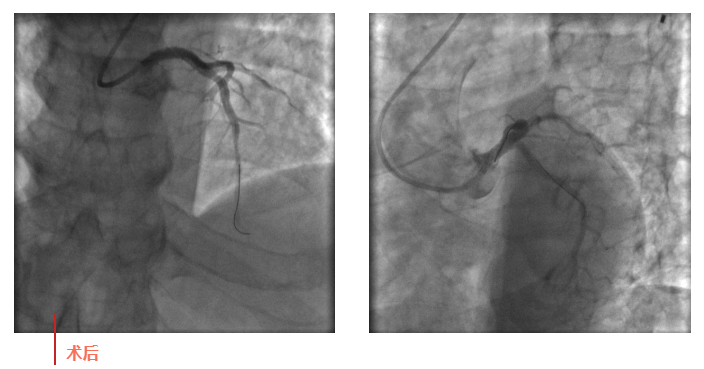

心血管內(nèi)科副主任徐先進(jìn)在主任助理農(nóng)彥林和主任汪念東的配合下行冠狀動(dòng)脈造影,結(jié)果如術(shù)前判斷一致,左主干重度狹窄,患者命懸一線。對(duì)團(tuán)隊(duì)緊急處置非常信任的李阿姨,毫無(wú)疑慮地聽(tīng)取了術(shù)者的建議,同意在血管內(nèi)超聲(IVUS)的精準(zhǔn)指導(dǎo)下,在患者左主干內(nèi)植入一枚支架,成功拯救了患者的生命。

術(shù)后,患者轉(zhuǎn)入心血管內(nèi)科CCU病房,在IABP泵的支持下渡過(guò)了危險(xiǎn)期。李阿姨紅著眼眶坐在床邊,仍心有余悸,“還好有你們?。≌媸翘x謝了!”經(jīng)過(guò)心血管內(nèi)科團(tuán)隊(duì)的精心治療和護(hù)理,患者現(xiàn)已康復(fù)出院。